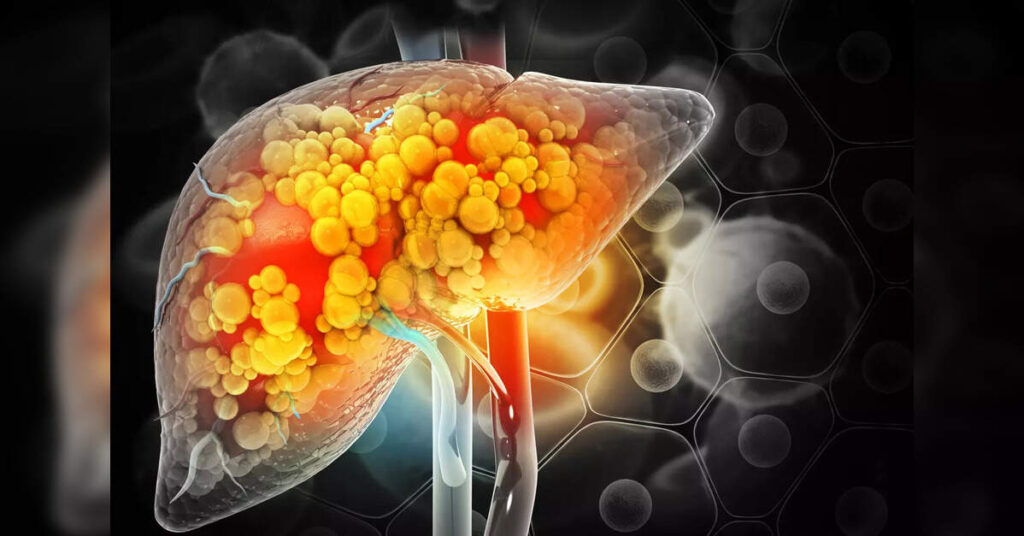

The liver is essential: humans need it to live. The liver contributes to metabolism and food storage, produces proteins that help with blood clotting and plays a vital role in the immune system.

At the cellular level, alcohol is a toxic substance that is metabolized (broken down) primarily in the liver. When the dose of alcohol is too high, liver cells become inflamed and damaged (liver inflammation is called hepatitis).

Over time, inflamed or damaged cells are replaced by fibrosis, which is the replacement of normal liver tissue with scar tissue, resulting in cirrhosis, or severe scarring and liver dysfunction. Cirrhosis can be fatal on its own and can also lead to liver cancer.

But alcohol isn’t the only key contributor to the rise in deaths from liver disease. Another is the rise of a condition called metabolic dysfunction-associated steatotic liver disease, or MASLD.

Despite the complicated name, MASLD is a type of liver disease that is caused by the same metabolic disturbances that have accompanied the rise of overweight and obesity coupled with inadequate physical activity. This is the same set of risk factors that have led to the increase in diabetes. So one can conceive of MASLD as the liver equivalent of diabetes.